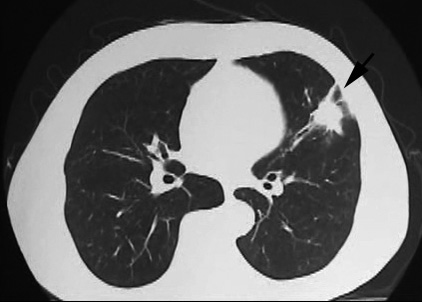

• X線検査では,通常,両肺の中・下部領域に多数の空洞化した転移性結節が認められる. 肺外への浸潤は極めて稀. 皮膚,中枢神経系,肝臓,腎臓などにも転移が見られる.

今月定期受診で1年ぶりにchest X-pを撮影. 両肺野に多発結節影が指摘されて受診となった.

chestX-pとCT.サムネイル画像クリックで大きな画像がみられます.